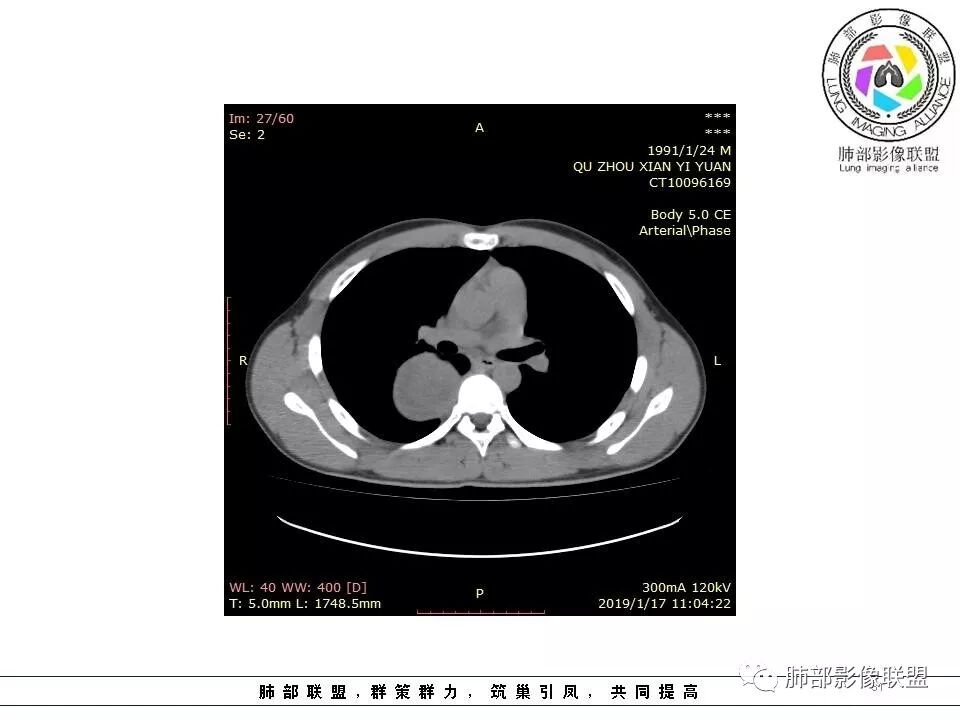

右后纵膈脊柱旁软组织占位,形态规则类圆,边缘光整,肺组织受压,胸膜尾,肋间动脉供血。中度不均匀延迟强化。

SFT,来源于壁层胸膜,建议穿刺活检。

右后纵膈脊柱旁软组织占位,边界清晰,光整,肺组织受压。胸膜被掀起,肋间动脉供血,中度不均匀延迟强化。考虑神经鞘瘤,不除外纤维瘤

右后纵膈脊柱旁软组织影,与纵隔结构分界不清,形态规则类圆,边缘光整,肺组织受压,胸膜尾,肋间动脉供血。肺动脉推移,中度不均匀延迟强化。考虑神经来源,神经鞘瘤,神经纤维瘤二者不易鉴别。

青年男性,间断胸痛;右侧脊柱旁可见一类圆形软组织密度影,密度欠均匀,增强扫描呈轻中度持续强化,邻近肺组织及肺动脉推移,可见肋间动脉供血,部分胸膜下脂肪可见,部分层面似见与右侧椎间孔相连。考虑后纵隔神经源性肿瘤。

青年男性,间断胸痛。右后纵膈脊柱旁软组织占位,形态规则类圆,边缘光整,肺组织受压,D字征,胸膜尾,肋间动脉供血。中度不均匀延迟强化。无支气管进入考虑来源于肺外、肿块与脊柱间未见明显脂肪间隙,考虑来源于胸膜外,考虑神经源性肿瘤,建议穿刺活检。

1.右上胸内脊柱旁类圆形肿块,质地似乎比较坚实,密度稍显不均,但未显示明确的坏死。

如此密度形态的病灶位于肺边缘首先应当想到孤立性纤维瘤,可相邻胸膜未见明显的异常强化和胸膜方向延伸。

2.肋间动脉病供血也提示肿块来自后纵隔?